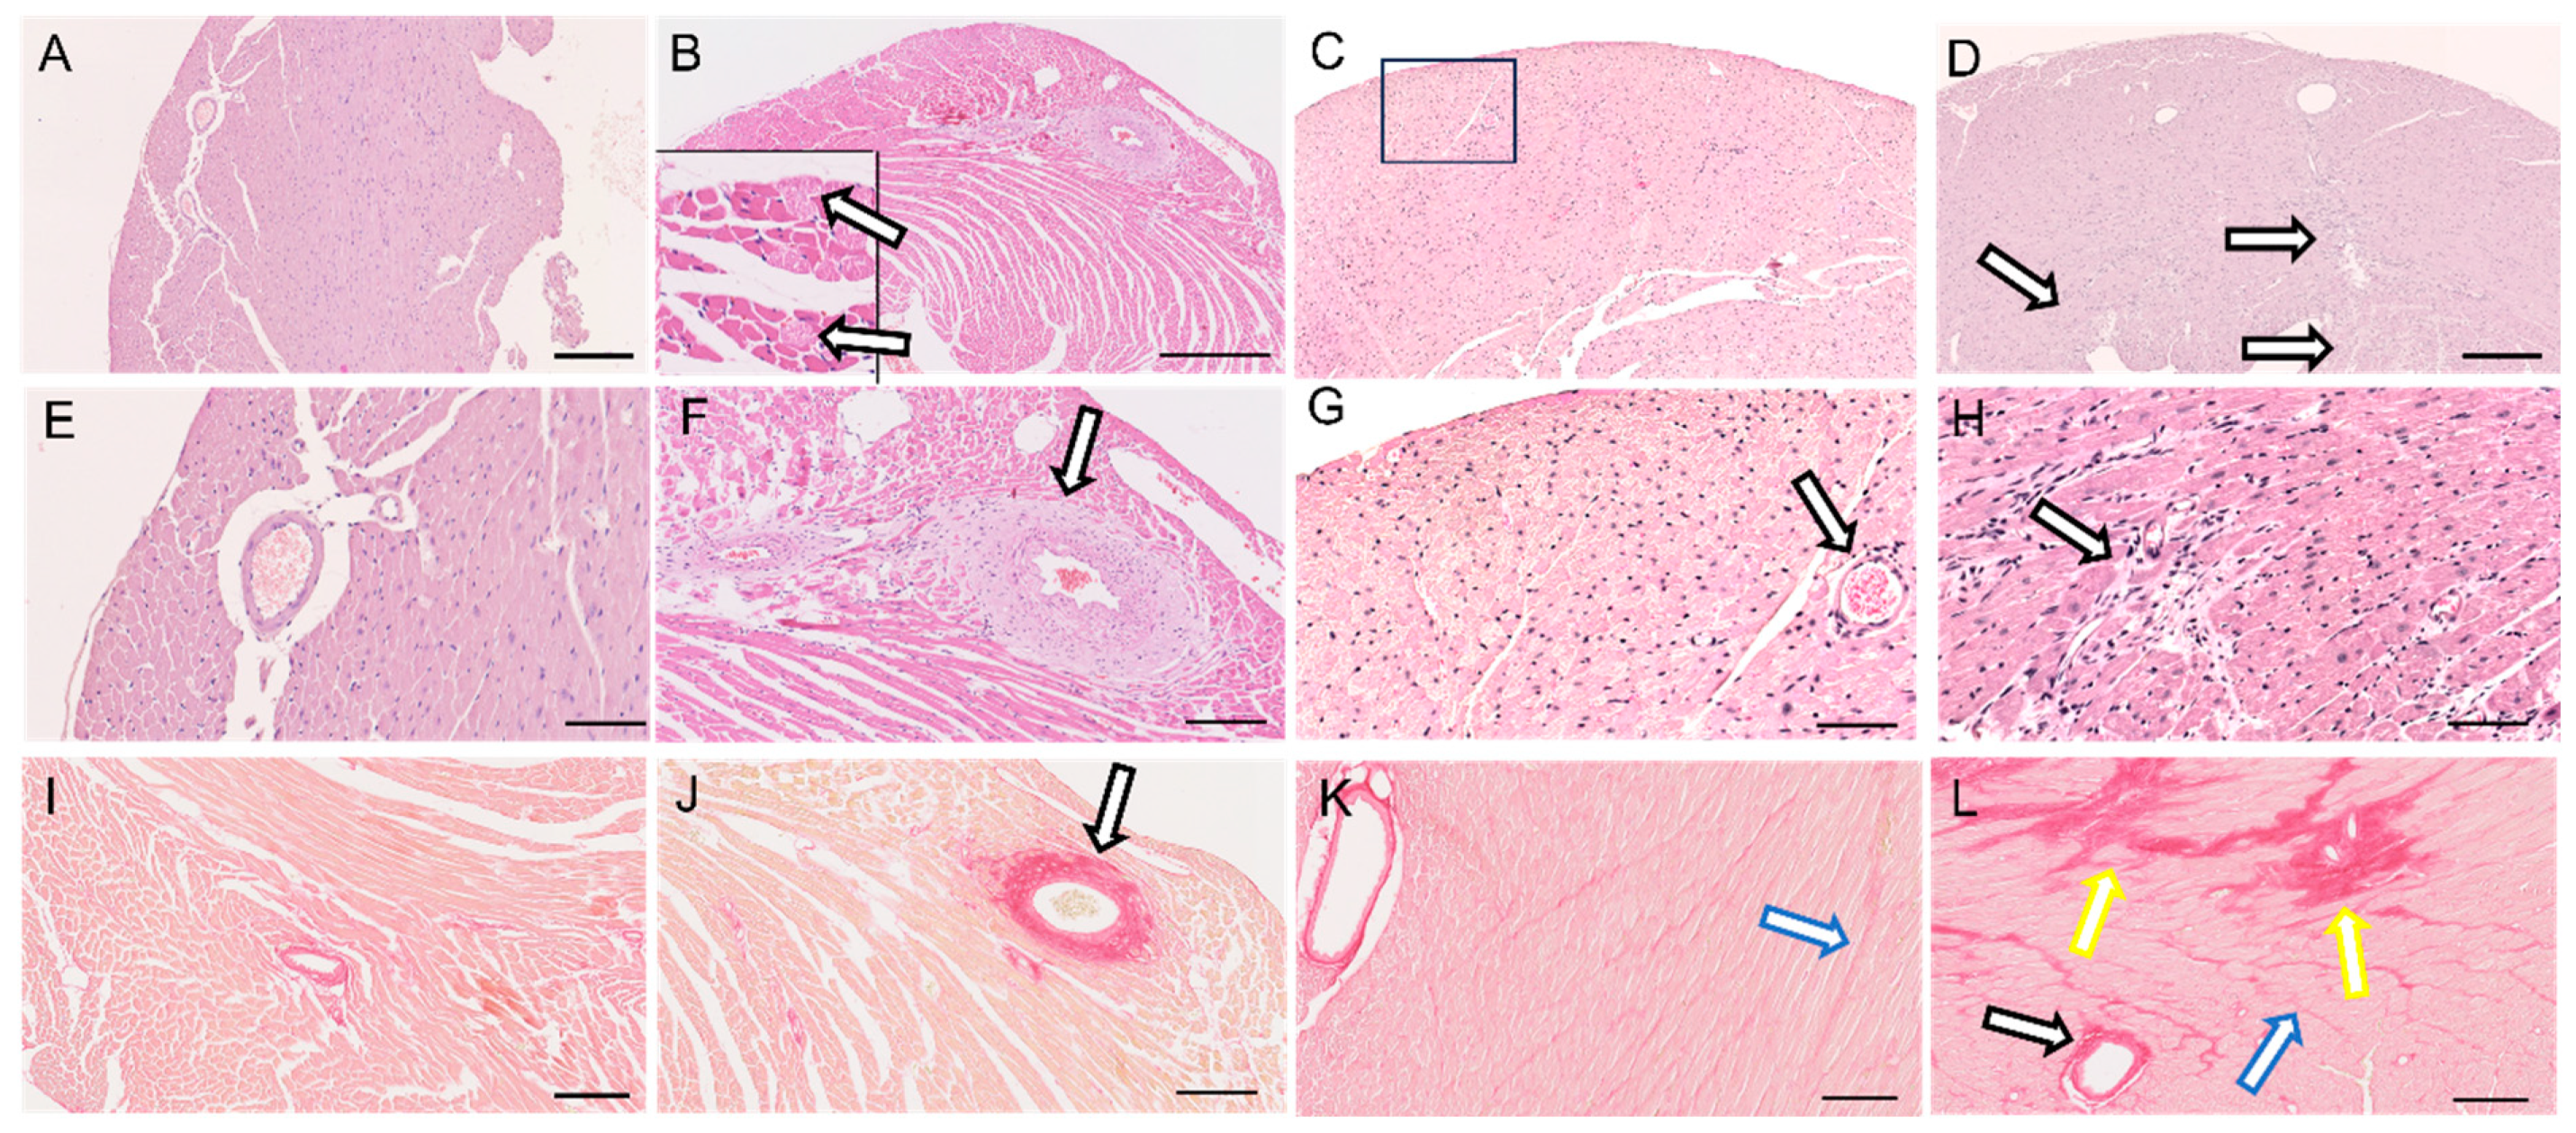

2.5. Histology and Morphometric Analyses

3.2. Heart Hypertrophy and Myocardial Remodeling